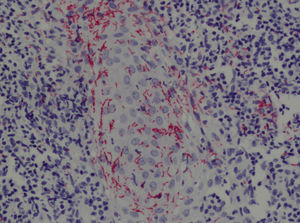

En el estudio histológico del caso 2 se observaba una hiperplasia epidérmica irregular y un denso infiltrado inflamatorio linfohistiocitario de distribución liquenoide con una marcada afectación de la unión dermoepidérmica. El inmunomarcaje demostró la presencia de numerosas espiroquetas que presentaban un marcado vasculotropismo y epiteliotropismo perifolicular (fig. 3).

Según Ackerman12 se clasificaría como una alopecia inflamatoria no cicatricial con presencia de un infiltrado dérmico linfohistiocitario perivascular y perifolicular con células plasmáticas9. En la alopecia areata se puede observar un patrón similar, pero existen una serie de hallazgos que son altamente sugestivos de alopecia areata, como la presencia de folículos pilosos miniaturizados, eosinófilos peribulbares y un infiltrado linfocitario en panal de abeja7,9,11. En estudios moleculares recientes se ha identificado al Treponema pallidum en los folículos afectos, hecho que apoya la teoría de una reacción inmunológica específica a los antígenos treponémicos7. Las técnicas inmunohistoquímicas pueden detectar la presencia de espiroquetas en el folículo piloso, generalmente en la regíon perifolicular y peribulbar, otorgando al treponema un papel patogénico directo como responsable de la alopecia13.